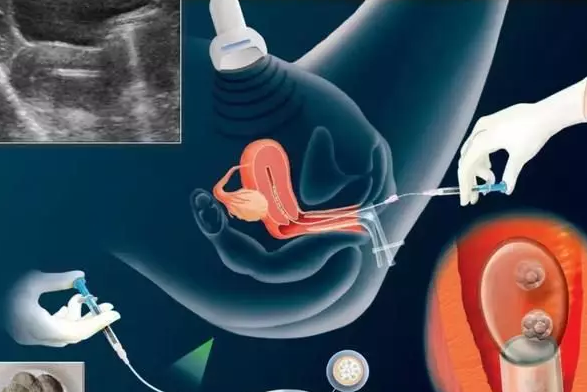

試管嬰兒在現代來說是很成熟的一種技術,對于治療不孕不育和生育難有很大的幫助,但是對于試管嬰兒這項技術,以及相關的知識,很對人并不太清楚,接下來八寶網小編就來說說有關于試管嬰兒相關知識。..

做試管嬰兒要滿足什么條件 試管嬰兒怎么做

現在很多人因為身體或著其它原因導致不孕,又非常想要孩子。那么試管其實是很好的選擇,那么除了考慮費用的問題